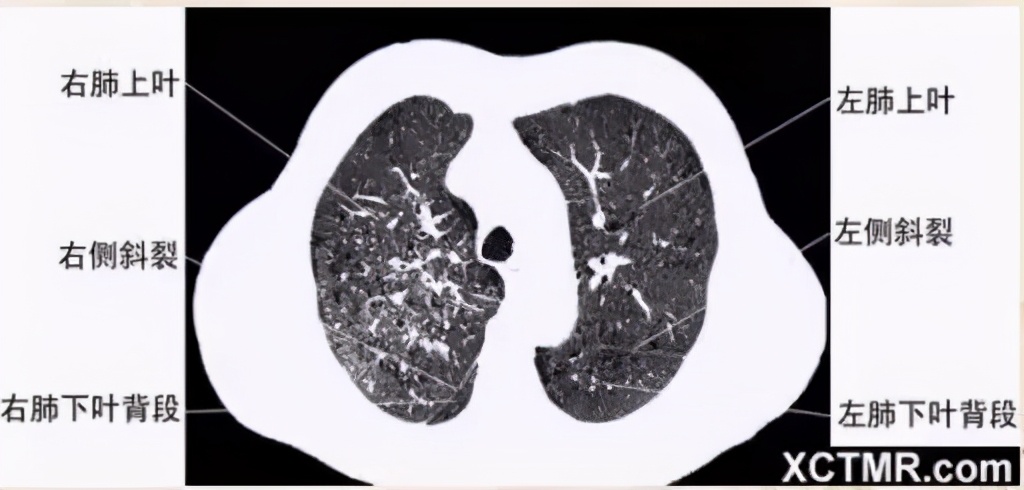

肺段划分